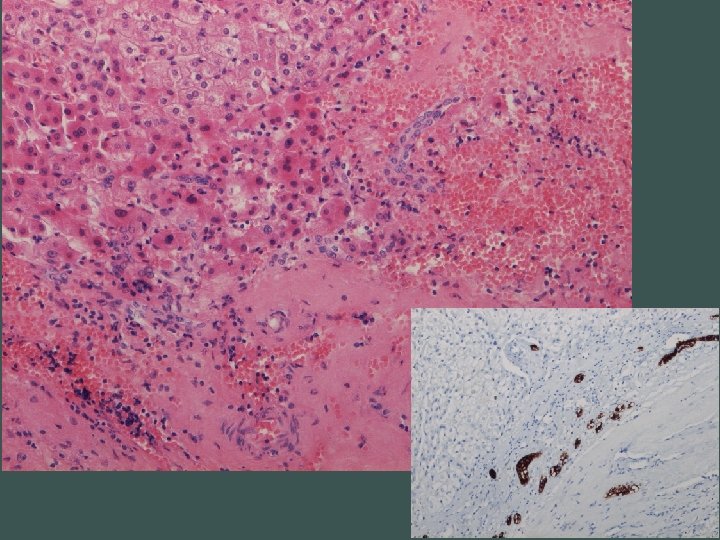

Naša diagnóza Segmentálna atrofia pečene, stage II / nodulárna elastóza pečene

Segmentálna atrofia pečene • zriedkavý pseudotumor • častejšie u žien, unifokálny • najčastejší príznak bolesť horného pravého kvadrantu • prevažne subkapsulárne • 1, 8 - 10 cm • abnormálne hrubostenné cievy (len intralezionálne), často trombotizované, rekanalizované • biliárne cysty

Stage 1 - 4 • 1 – kolaps parenchýmu so zachovaním portálnych polí, občasnými ostrovčekmi zachovaného parenchýmu a s duktulárnou reakciou • 2 – minimálna až žiadna duktulárna reakcia, zvýšená miera elastózy • 3 – takmer výlučne elastóza, občasné malé ostrovčeky hepatocytov • 4 – end stage, ložisko fibrózy

Abnormálne cievy • vyvolávajúci impulz ischémia?